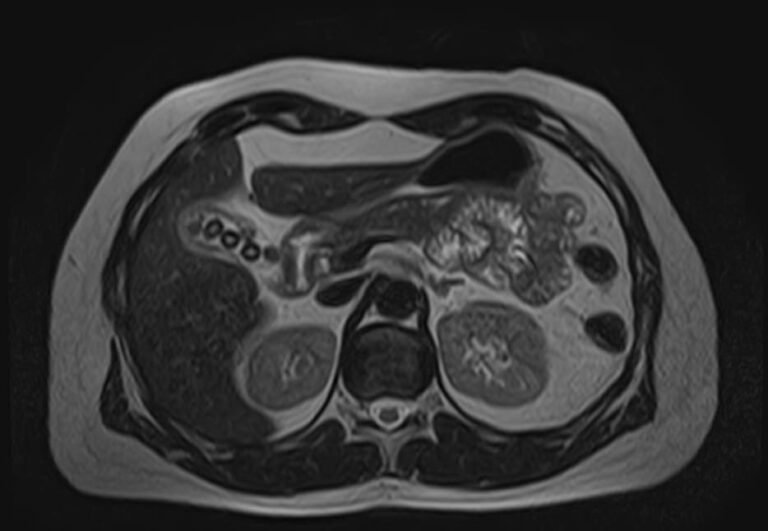

МРТ забрюшинного пространства является наиболее информативным, безопасным и доступным методом исследования, который позволяет оценить состояние органов, расположенных в данной анатомической зоне (почки, надпочечники, мочеточники), выявить возможные патологические процессы.

В клинике «Доступная медицина» установлен новейший высокопольный томограф экспертного уровня TOSHIBA VANTAGE TITAN 1,5 Тесла, на котором выполняется обследование органов забрюшинного пространства. За счет высокой индукции магнитного поля аппарат при сканировании создает изображения на плоскости превосходной четкости, затем с помощью компьютерных приложений данные преобразуются в изображения трехмерного формата, что обеспечивает точность и достоверность диагностики.

МРТ брюшного и забрюшинного пространства направлено на определение состояния нескольких органов, по результатам диагностики визуализируют:

- Аорта и нижняя полая вена. В рамках диагностики структурных патологий.

- Мочеточники. Часть мочевыделительного тракта. Из-за малого диаметра и особенностей строения, визуализируются с трудом. Томография — основной способ диагностики патологических процессов.

- Двенадцатиперстная кишка (частично). При параллельном обследовании органов брюшной полости картина становится более полной и понятной.

- В районе брюшной полости и забрюшинного пространства располагаются ответвления крупных сосудов.